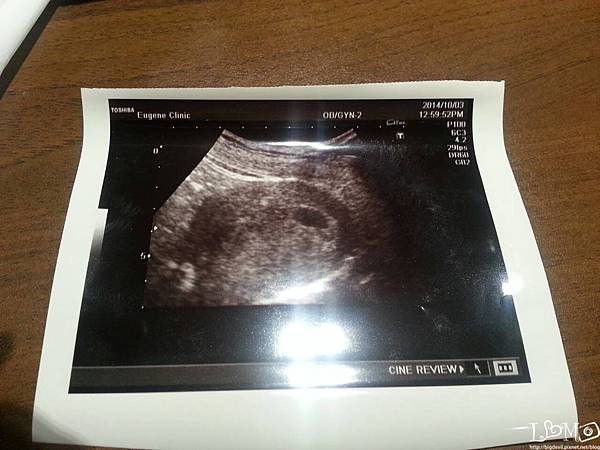

第一次產檢時,皮蛋看到了寶寶胎囊的照片

那黑黑一個的胎囊,5W大的狀態,還沒有心跳

醫生看似隨興地告訴我別太緊張,正常吃喝避免生食

然後就約了兩周後看心跳